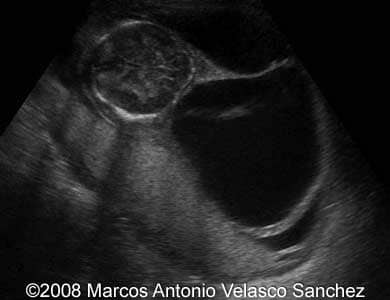

This is a 17-year-old woman scanned at 15 weeks of pregnancy. The ultrasound revealed massive septate cystic hygroma and subcutaneous edema of the fetus.

Images 1-6: 2D scans of the fetal neck with massive septate cystic hygroma.